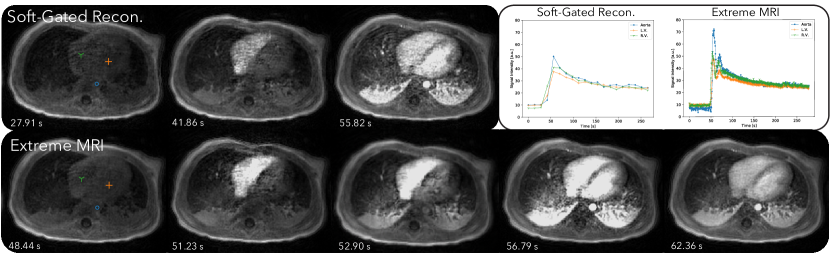

Figure 4 and Supporting Information Video S4 and S6 compare the proposed method with the soft-gated reconstruction. Regular respiratory motion can be observed in the proposed reconstruction in Video S4. Slight movements of the subject’s left arm can be seen from the video right before the contrast enhancements and toward the end of the scan. This can also be visualized in the 3D rendered Supporting Information Video S1. Contrast enhancements can be seen starting from the right ventricle, to the lung, then the left ventricle, and to the aorta, whereas the soft-gated reconstruction merges together the temporal changes of the lung, the left ventricle and the aorta. The signal intensity plots for the proposed reconstruction also show much higher peaks when contrast is injected, which is physiologically accurate. In comparison, the soft-gated reconstruction signal curves appear to be smoothed.

Figure 4, 6, and 8 all show that the proposed reconstruction displays much finer dynamics that are not represented in soft-gated reconstructions with low frame-rates. Distinct phases of contrast enhancements in different organs can be seen, which are more physiologically accurate. The benefits of higher temporal resolution can also be seen from signal intensity curves. In particular, signal intensity peaks of the aorta are much higher in the proposed reconstruction, but are averaged out in the soft-gated reconstruction. While bulk motion still affects the overall image quality as shown in Figure 6, the proposed reconstruction allows us to retrospectively adjust for bulk motion when computing the signal intensity curves, which can be useful for quantification purposes.